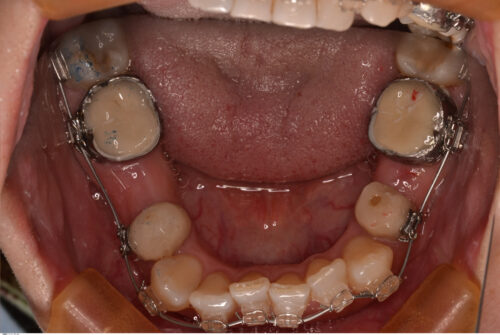

第2小臼歯は全て先天性欠損で下顎にはブリッジが入っています。

下顎は骨が硬いのでなかなか動いてくれません。